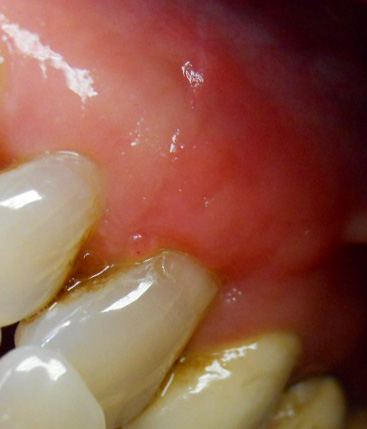

Il paziente si presenta alla mia attenzione lamentando ipersensibilità dentinale e recessione antiestetica in zona 23.

Dopo valutazione dell'altezza e dello spessore adeguato di gengiva aderente e fornice sufficientemente profondo a livello della recessione (1a classe di Miller) si opta per l'intervento di spostamento coronale di lembo a spessore misto, senza innesto.

(Intervento e foto eseguiti da me in 1h)